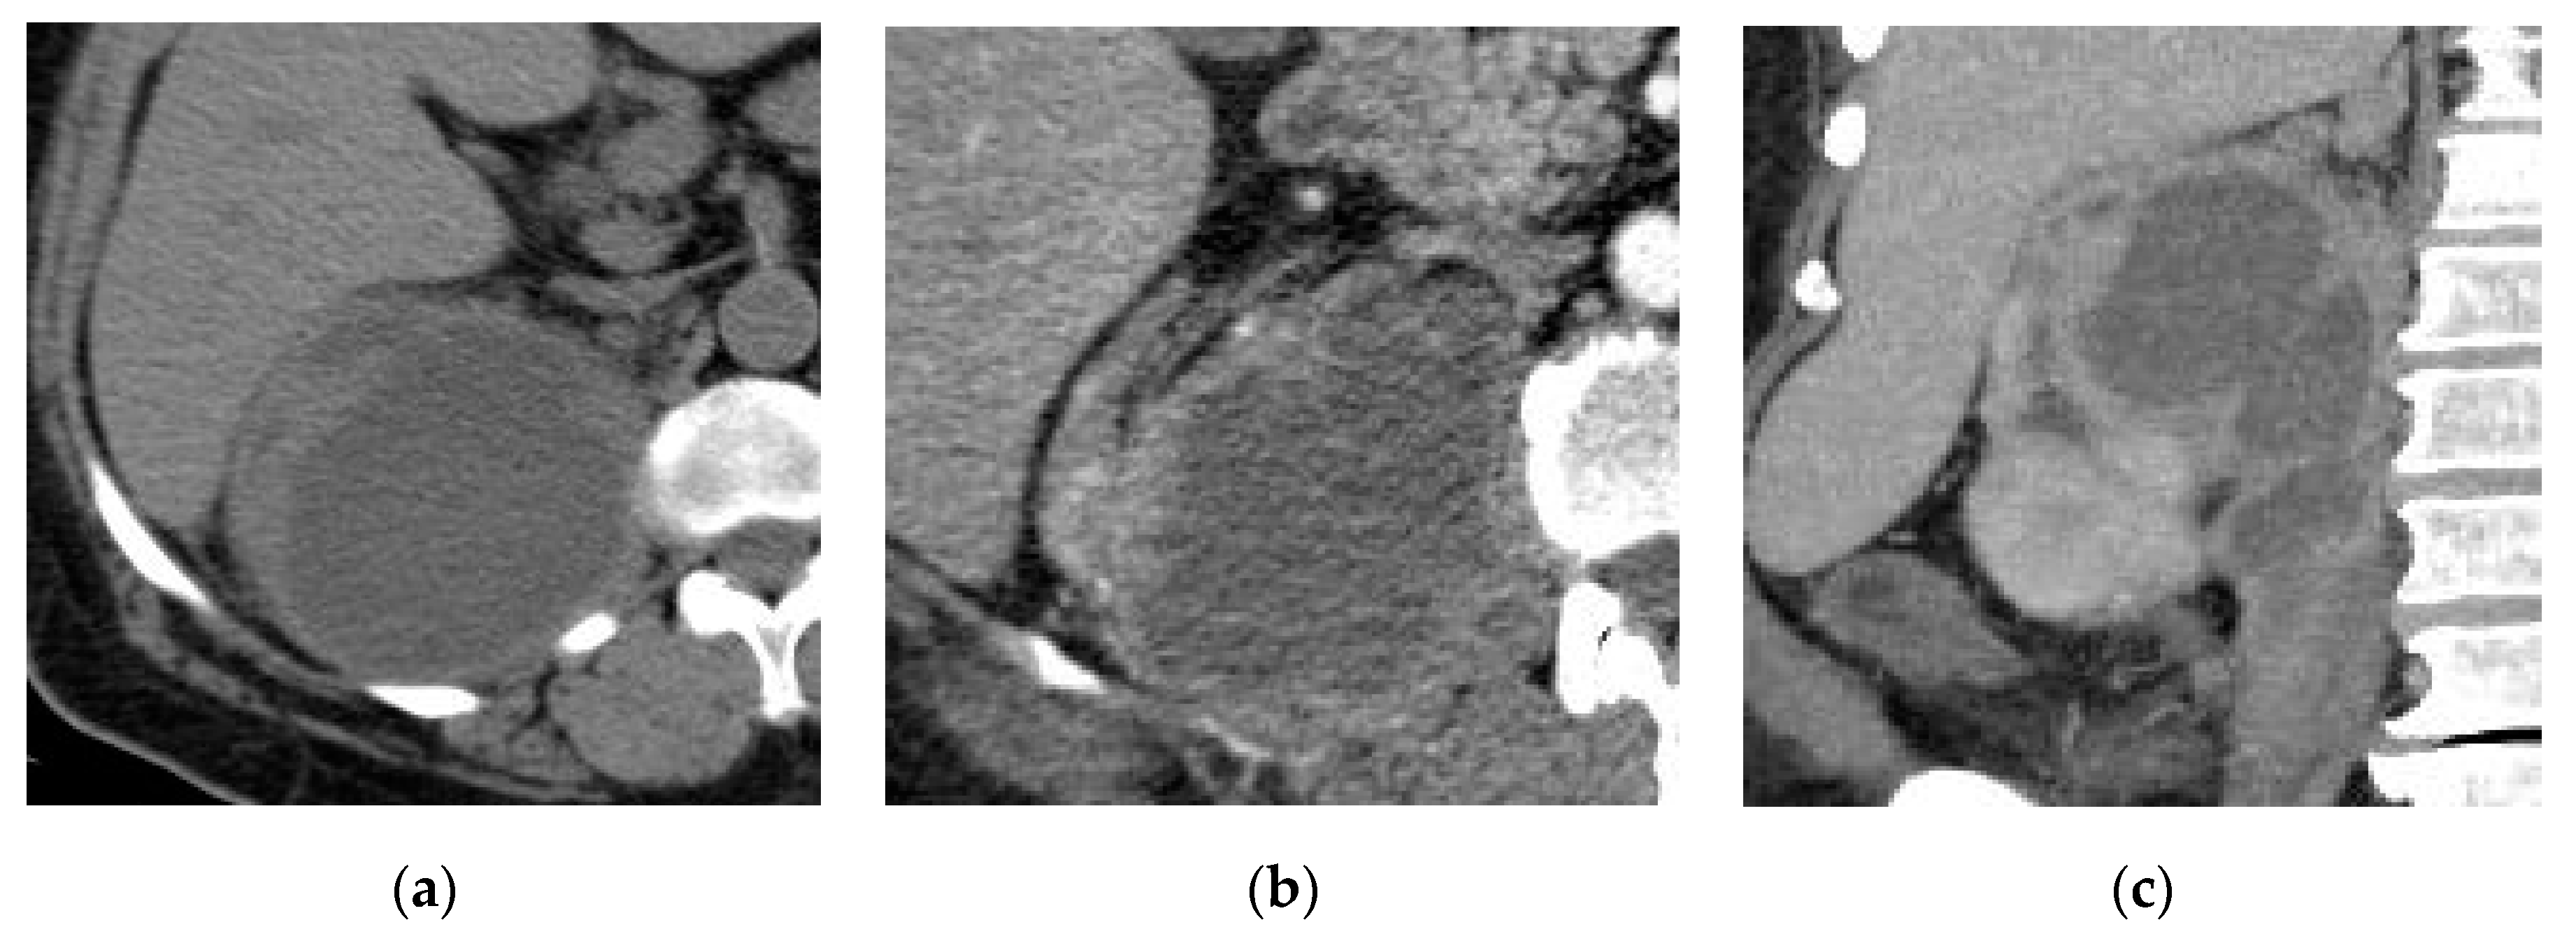

2.5. Xanthogranulomatous Pyelonephritis (XGP)

| Xanthogranulomatous Pyelonephritis | Non-functioning enlarged kidney, obstructing stone within a non-dilated renal pelvis, expansion of the calyces, and inflammatory changes in the perinephric fat. |